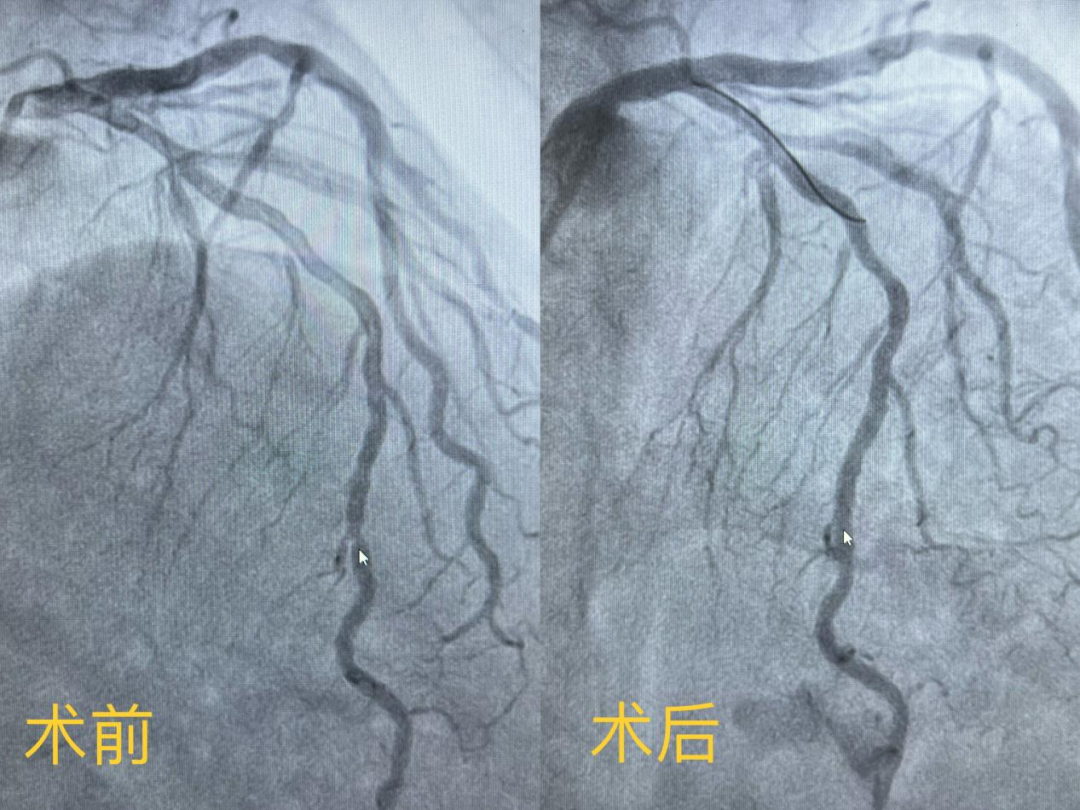

女性患者,因反復胸痛10余年就診我院,心內科團隊為其行冠狀動脈造影確診冠心病,左前降支遠段中部90%狹窄,需要行冠脈支架植入治療。在與患者及家屬溝通時,患者家屬提到,他們了解得知臨床有一種新型的可吸收支架,植入體內后支架能完全被降解和吸收,希望能用這種新型的支架進行手術治療。由于生物可吸收支架有著嚴格的適應癥,心內科醫護團隊經過嚴格篩選評估及反復討論后制定了詳細的手術方案,為該患者冠狀動脈狹窄處精準植入一枚生物可吸收支架,手術過程順利,術后造影顯示支架釋放貼壁良好,無殘余狹窄,患者胸悶痛癥狀完全消失,術后3天順利出院。

微信圖片_20221130172539.png

(手術前后造影圖)